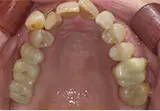

| 年齢/性別 | 40代女性 |

| 主訴 | 右上の詰め物が取れた |

| 治療内容 | 歯周病とむし歯の治療を目的に来院。左下の奥歯は根の状態が悪く、病変も大きかったため保存が困難と判断。 インプラント治療を実施しました。 |

| 治療期間 | 4か月 |

| 費用 | 566,500円税込 |

| リスク・副作用 | 炎症反応によって術後に腫れが生じることがあります。その程度は、手術の範囲や方法によって異なりますが、多くの場合、時間の経過とともに徐々に治まります。 ごく稀に、下顎奥歯の外科手術後に、唇や顎に痺れを感じることがあります。 |